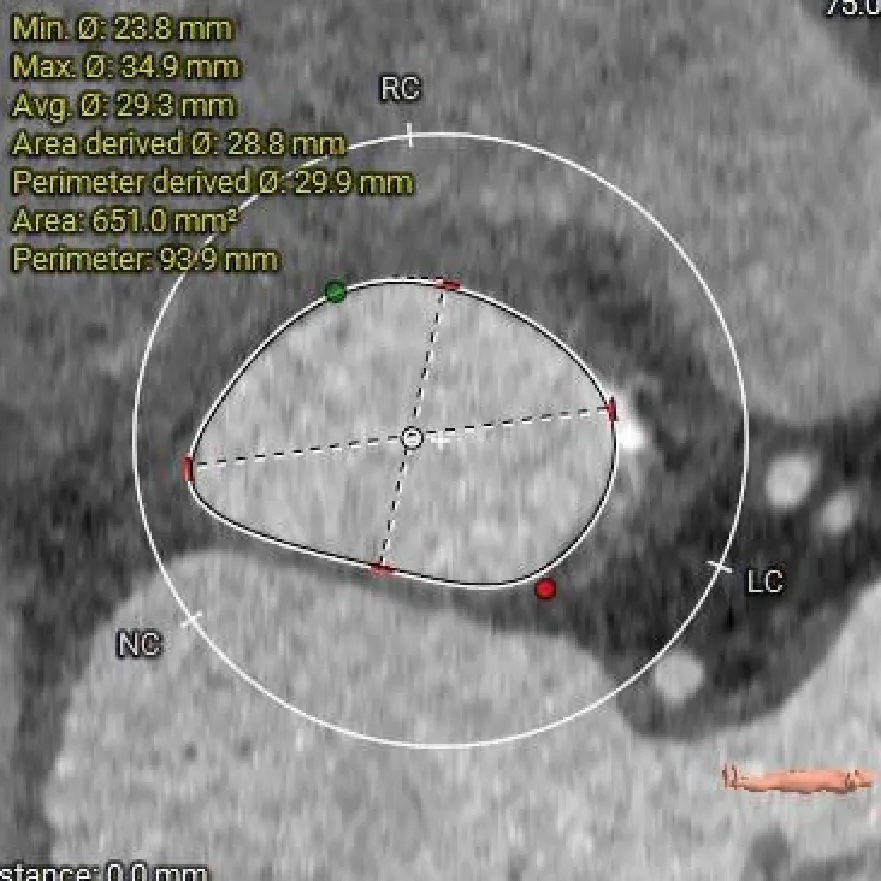

术前CT分析

主动脉根部测量

Annulus-收缩期

30.3mm

Annulus-舒张期

29.9mm

LVOT

30.8mm

sinus

STJ

46.1mm

AAO

53.7mm

Type-0型二叶瓣

瓣环径约30.3mm

微敞口型流出道

瓣叶增厚

交界缘钙化分布

瓦氏窦扩张

升主瘤样扩张

瓣上结构测量

瓣上 2mm

瓣上 4mm

30.2mm

瓣上 6mm

瓣上 8mm

29.5mm